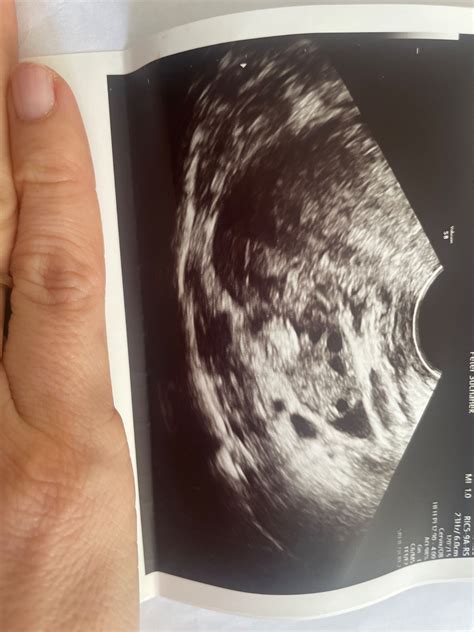

- Dozrievajúce a zrelé folikuly: Tieto folikuly dosahujú veľkosť 2 cm a vystupujú nad povrch vaječníka. Miesto uloženia oocytu v zrelom folikule sa nazýva ovulačný hrbolček (cumulus oophorus).

Po ovulácii, teda prasknutí folikulu, sa z jeho steny začína tvoriť žlté teliesko (corpus luteum) z buniek theka a granulózy. Na jeho tvorbe sa podieľajú luteínové bunky, ktoré vznikajú z buniek granulózy a theca interna. Tieto bunky sa rýchlo množia a vypĺňajú dutinu prasknutého folikulu, čím vzniká žlté teliesko, ktoré funguje ako žľaza s vnútornou sekréciou.

Žlté teliesko má zvyčajne guľovitý alebo vajcovitý tvar, s výnimkou oviec a kôz, kde má tvar trojuholníka. Jeho priemer je 1,5-2 cm a na jeho povrchu sa nachádza priehlbina, ktorá vznikla v mieste prasknutia folikulu. Farba žltého telieska sa počas vývoja mení: